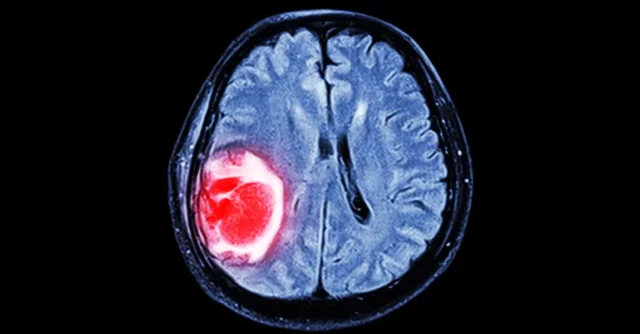

أورام الدماغ الحميدة أو الخبيثة لها مشاكلها الخاصة. نحن نطلق على أورام الدماغ اسم الآفات التي تشغل الفراغ ، وإذا تخيلت أن الدماغ عبارة عن صندوق مغلق فإن الورم المتنامي داخل الصندوق يضغط على أنسجة الدماغ السليمة ، وهذا يدل على أول إشارة إلى وجود خطأ ما

أصبحت أمراض القلب والأوعية الدموية (السكتة الدماغية) أكثر شيوعًا ومن المهم أن نعرف شيئًا عن الأعراض الأولية لهذا المرض. السكتة الدماغية هي مرض يصيب الأوعية الدموية التي تزود الدماغ بالدم. يتكون دماغنا من أربعة أجزاء رئيسية: نصف الكرة المخية الأيمن ، ونصف الكرة المخية الأيسر، والمخيخ ، وجذع الدماغ. كل جزء من الدماغ مسؤول عن وظائف مختلفة.